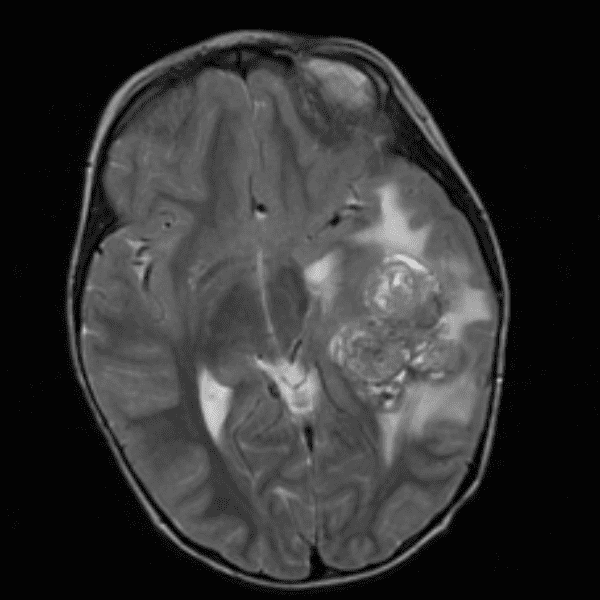

Classic Cases